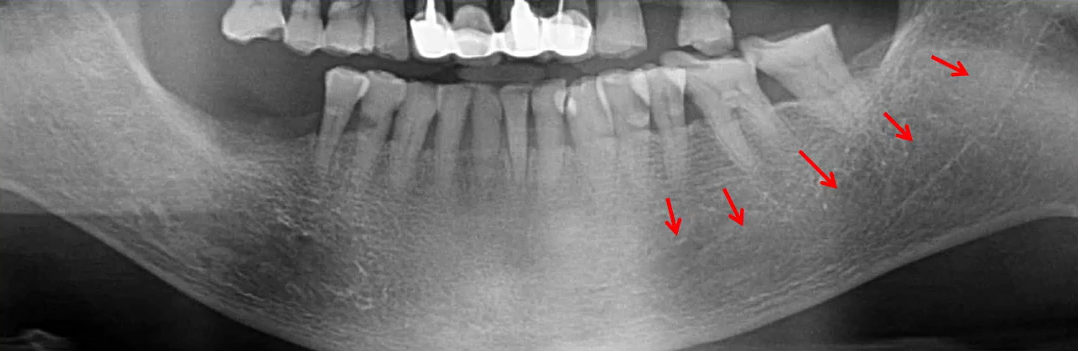

因为曲面断层片反映的是上下颌牙齿、上颌窦、关节,在一张片子中所展示的解剖结构较多。比如刚才的片子,最容易诊断的是右下6远中邻面深龋合并根尖周炎,左下有埋伏的多生智齿,右侧是垂直智齿。

左、右下5根方有低密度影,一般认为是颏孔位置,左右对称进行观察可以排除一些疾患。